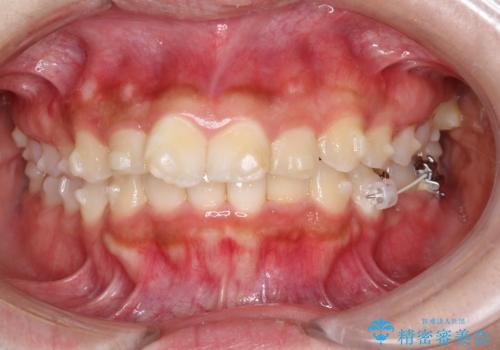

目立たない矯正で中等度の叢生を改善

- 歯のデコボコ(叢生)を気にされて来院されました。精密な検査の結果、中等度の叢生と診断。患者様のご希望に合わせ、透明で目立ちにくい**インビザライン(マウスピース矯正)**による治療計画を立案しました。歯を抜かずに、歯列弓(歯が並ぶアーチ)を少しずつ拡大することで、歯が並ぶスペースを確保し、叢生を改善することを目指します。

今回の矯正治療では、透明なマウスピース型の装置インビザラインを使用しました。この装置は目立ちにくく、取り外しが可能なため、食事や歯磨きも普段通りに行えます。治療は、緻密に計算された治療計画に基づき、段階的に作製されたマウスピースを交換していくことで、歯列弓全体を徐々に広げていきました。この歯列弓の拡大により、不足していたスペースを確保し、歯のデコボコを効果的に解消。抜歯することなく、整った美しい歯並びと良好な咬み合わせを獲得していただけました。